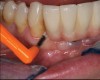

The first step in preventive strategies must be to perform a correct diagnosis of the peri-implant condition by accurately assessing the health of the peri-implant hard and soft tissues through periodontal probing and periapical radiographs at the time of definitive prosthetic installation. These measurements should be considered the baseline diagnosis and, therefore, represent a true starting point for evaluating the changes on the radiographic bone levels and probing pocket depths (PPD) at future recall appointments (Figure 1 and Figure 2).6 Although probing depth measurements of peri-implant tissues do not have the same diagnostic value as probing periodontal tissues, there is evidence that BOP is the most objective sign of peri-implant tissue inflammation; significant deepening of PPD compared with baseline measurements is also a sign of disease that indicates the need to perform a radiographic evaluation (Figure 3 through Figure 5).6,10,11

Fig 3. Peri-implant mucositis: mucosal inflammation.

Figure 3

Fig 4. Bleeding on probing.

Figure 4

Fig 5. Radiograph showing no bone loss.

Figure 5